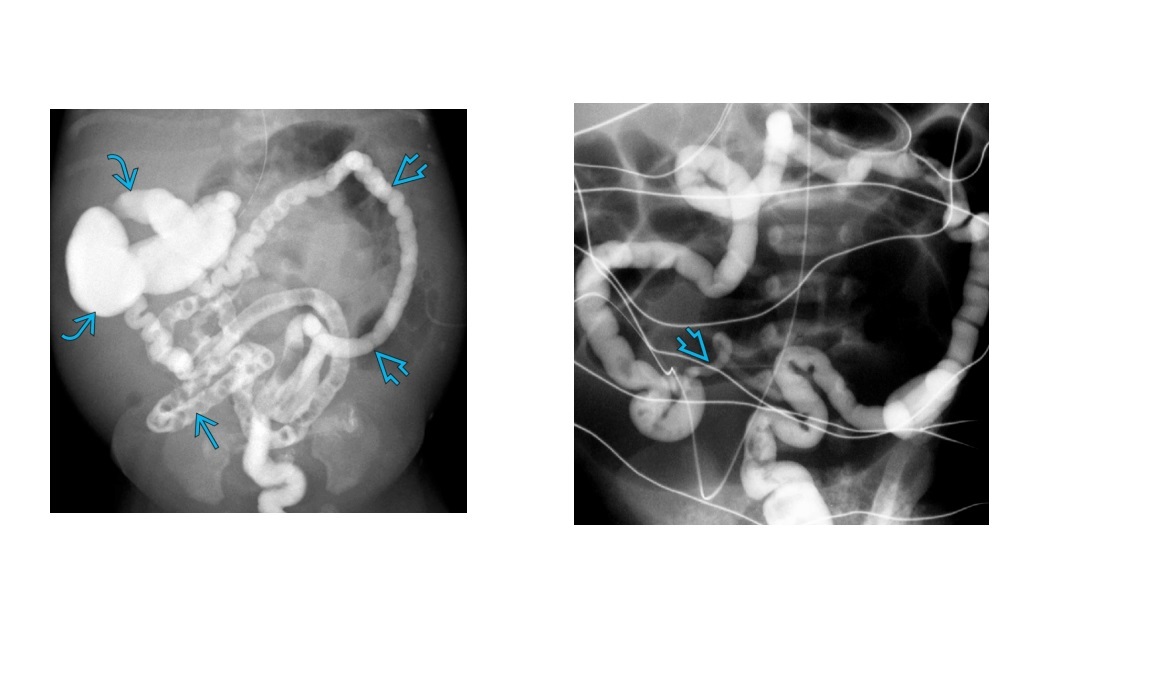

Main causes for Neonatal distal intestinal obstruction with microcolon?

A. Meconium Ileus

Meconium impacted at the terminal ileum. Linked to CF.

On WSCE - outlines meconium pellets obstructing terminal ileum.

B. Ileal atresia

On WSCE - Blind end of contrast column in ileum = Ileal atresia

C. Total colonic Hirschsprung disease

Main causes of neonatal distal intestinal obstruction with small distal /left colon?

A. Meconium plug syndrome (neonatal small left colon) Nonpathological transient functional obstruction at the **proximal descending colon****. +/- if water souble contrast isnt therapeutic then - Rectal biopsy to exclude long segment HD B. Colonic atresia WSCE - blind ending small caliber distal colon (can be more proximal) C. Hirschsprung's disease WSCE - Classically short rectosigmoid segment = small calibre rectum and dilated sigmoid (rectosigmoid ration <1). Long segment - Transition zone from the small distal colon to the dilated proximal colon ****suction biopsy below this transition point.**